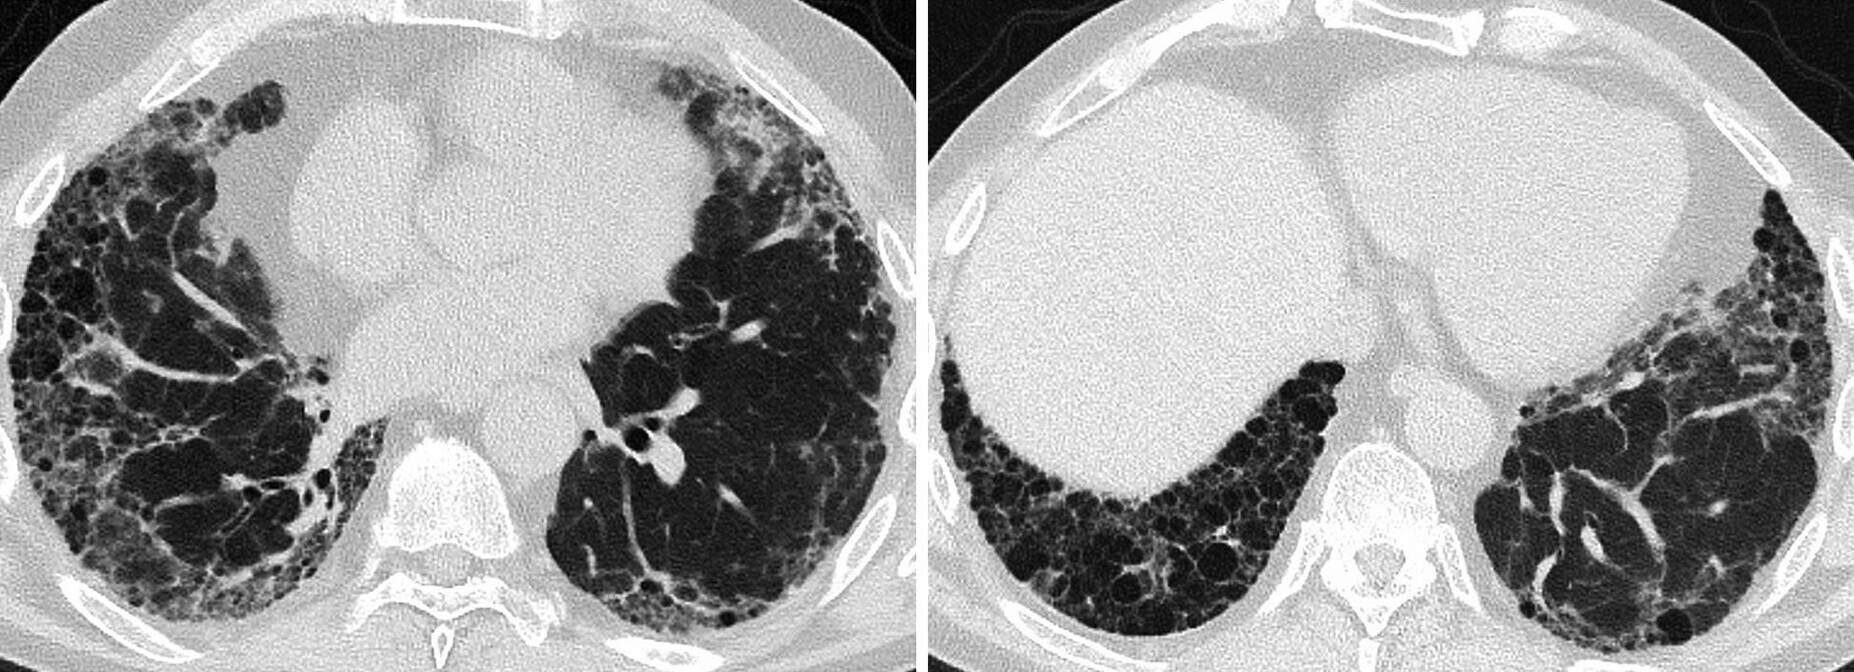

Lungenfibrose bei rheumatoider Arthritis

Ein 64-jähriger Mann, Exraucher, präsentiert sich mit einer symmetrischen Polyarthritis unter Beteiligung der Hand- und Fingergelenke. Es besteht keine systemische Entzündung (CRP und BSR normal). Rheumafaktoren (158IU/ml, normal <3,5IU/ml) und CCP-Ak (63U/ml, normal <7U/ml) sind erhöht. Entsprechend den Kriterien des American College of Rheumatology (ACR) von 2010 gilt die Diagnose einer RA mit 9 Punkten (mind. 6) als gesichert. Radiologische Veränderungen an Händen und Füssen bestehen nicht. Der Disease Activity Score (DAS) 28 wird mit 4,25 berechnet, was eine aktive RA anzeigt (>2,6). Er berichtet weiterhin über eine Belastungsdyspnoe und Husten. Die Lungenfunktion zeigt eine mittelschwere restriktive Ventilationsstörung mit eingeschränkter Diffusionskapazität.

In der BAL stellt sich ein unspezifischer Befund dar (leicht erhöhte Gesamtzellzahl, 43,7% Granulozyten, 14% eosinophile Granulozyten).

Das CT der Lunge zeigt basal betonte und periphere retikuläre Verdichtungen, teils mit umgebendem Milchglasmuster und subpleuralen Tranktionsbronchiektasen, mit möglichem UIP-Muster vereinbar (Abb. 166.1).

Abb. 166.1 Lungenfibrose bei rheumatoider Arthritis.

(Quelle: Dr. Jörg-Thomas Kluckert, Netzwerk Radiologie, Kantonsspital St. Gallen, Schweiz)